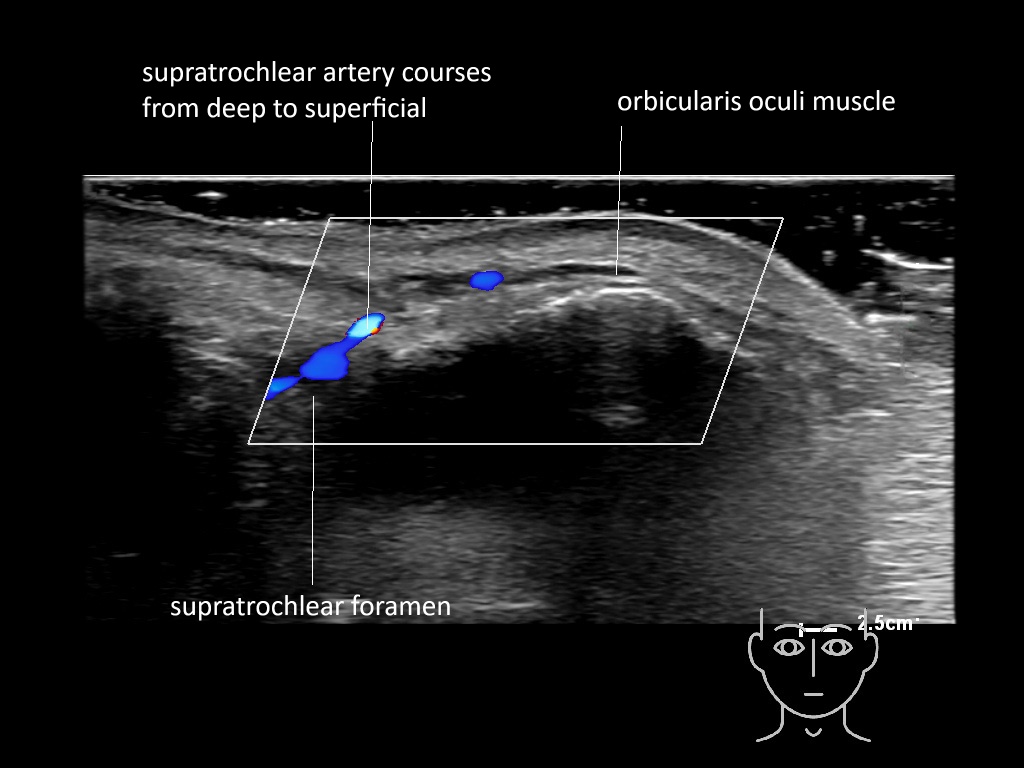

In this section you will learn more about the different layers of the face with the use of ultrasound. When you click on the secondary ultrasound image, you will see the different structures as an overlay. This will help to train yourself to recognize the different layers of the face.

Study the first image to recognize the different layers. If you are sure about the layers, swipe to the second image to view the answer (if applicable).